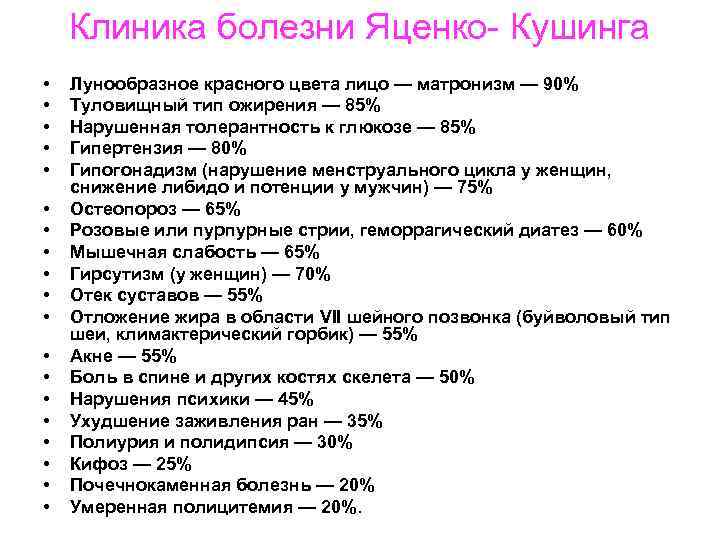

Клиника болезни Яценко Кушинга • • • • • Лунообразное красного цвета лицо — матронизм — 90% Туловищный тип ожирения — 85% Нарушенная толерантность к глюкозе — 85% Гипертензия — 80% Гипогонадизм (нарушение менструального цикла у женщин, снижение либидо и потенции у мужчин) — 75% Остеопороз — 65% Розовые или пурпурные стрии, геморрагический диатез — 60% Мышечная слабость — 65% Гирсутизм (у женщин) — 70% Отек суставов — 55% Отложение жира в области VII шейного позвонка (буйволовый тип шеи, климактерический горбик) — 55% Акне — 55% Боль в спине и других костях скелета — 50% Нарушения психики — 45% Ухудшение заживления ран — 35% Полиурия и полидипсия — 30% Кифоз — 25% Почечнокаменная болезнь — 20% Умеренная полицитемия — 20%.

Клиника болезни Яценко Кушинга • • • • • Лунообразное красного цвета лицо — матронизм — 90% Туловищный тип ожирения — 85% Нарушенная толерантность к глюкозе — 85% Гипертензия — 80% Гипогонадизм (нарушение менструального цикла у женщин, снижение либидо и потенции у мужчин) — 75% Остеопороз — 65% Розовые или пурпурные стрии, геморрагический диатез — 60% Мышечная слабость — 65% Гирсутизм (у женщин) — 70% Отек суставов — 55% Отложение жира в области VII шейного позвонка (буйволовый тип шеи, климактерический горбик) — 55% Акне — 55% Боль в спине и других костях скелета — 50% Нарушения психики — 45% Ухудшение заживления ран — 35% Полиурия и полидипсия — 30% Кифоз — 25% Почечнокаменная болезнь — 20% Умеренная полицитемия — 20%.